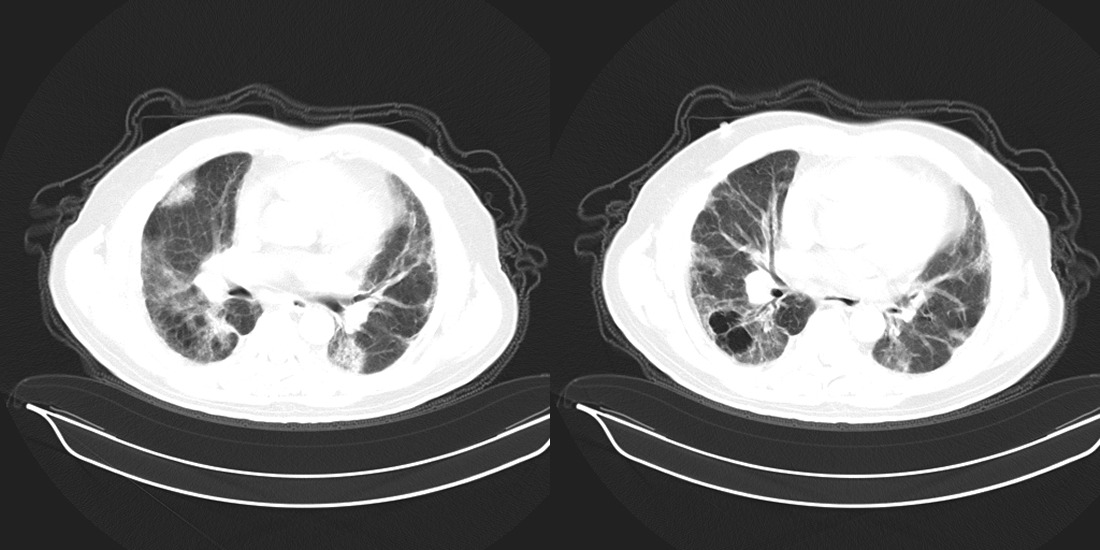

以下是引用zsl6918在2008-2-14 12:15:00的发言:[br]慢支并感染,肺气肿,肺间质纤维化,肺动脉高压。

以下是引用liuyue在2008-2-14 17:25:00的发言:[br]慢支并感染,肺气肿,肺间质纤维化,肺动脉高压 .肺大泡.[br]

以下是引用随光逐影在2008-2-15 11:10:00的发言:[br]1)慢性支气管炎并肺部感染。2)肺间质纤维化。3)肺气肿(多发性肺大泡形成)。4)肺动脉高压。